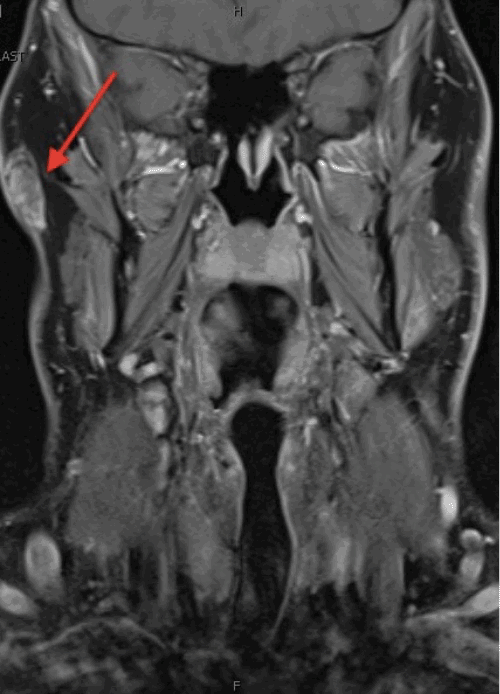

On physical examination, a 3 cm, non-tender, mobile, soft subcutaneous mass was palpated in the right preauricular region. Initial ultrasonography characterized the lesion as a hyperechoic soft tissue mass. Subsequent magnetic resonance imaging (MRI) revealed a well-circumscribed, non-specific lesion confined to the superficial soft tissues of the right preauricular area, without evidence of involvement of the underlying parotid gland or external auditory canal (Figure 1).

Figure 1. MRI of Preauricular Lipoblastoma. Published with Permission

Coronal T1-weighted fat-suppressed (FS) image post-contrast, illustrating the lesion (arrow) with peripheral and some internal enhancement, confirming its superficial location without invasion of the parotid gland or external auditory canal